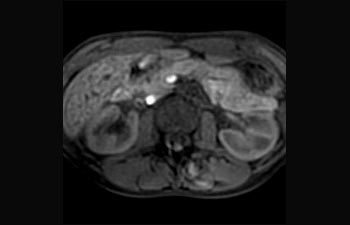

Encuentre la aplicación clínica adecuada a sus necesidades